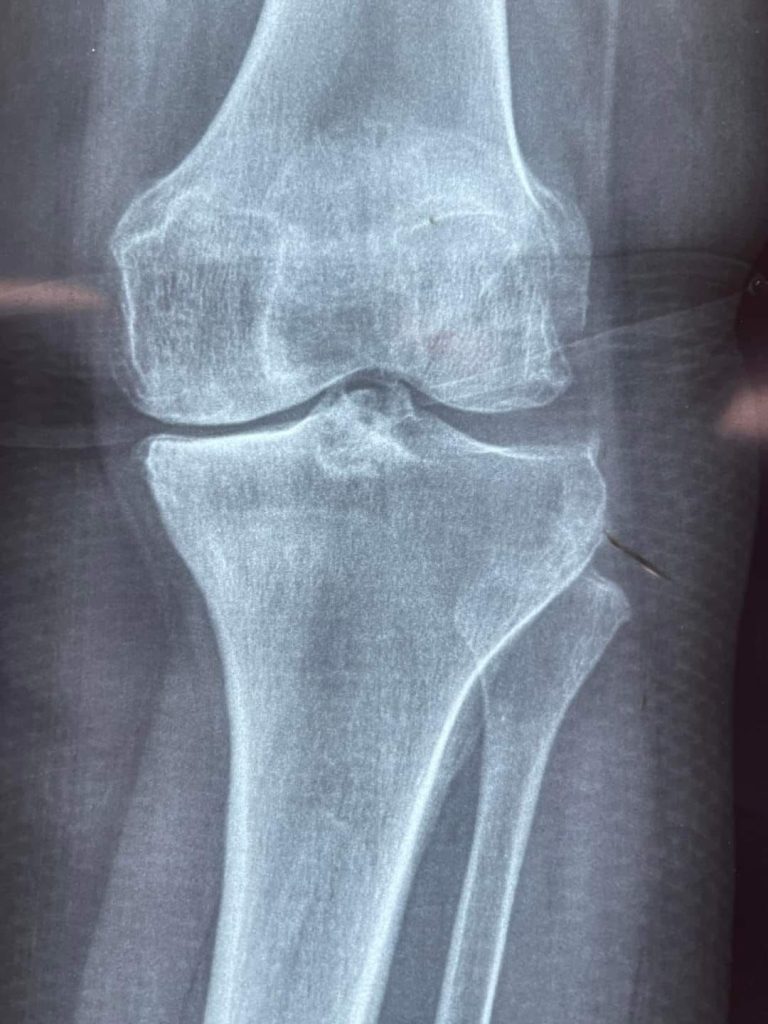

Dio inicio la jornada gratuita de cirugías de rodilla, que beneficia a 40 personas y que se realizarán en dos hospitales ubicados en Tepic: el Hospital de la Mujer, donde se atenderá a 20 mujeres, y en la UNEME, donde se llevarán a cabo las otras 20 cirugías.

Un beneficio gestionado por la doctora Beatriz Estrada Martínez presidenta del Sistema DIF Nayarit, quien destacó la importancia de este programa, mencionando que las cirugías son completamente gratuitas y se llevan a cabo con el apoyo de diversos organismos y profesionales de la salud de Nayarit, explicó la titular de la asistencia social en la entidad.

“Estamos recibiendo el apoyo de las prótesis por parte del Patronato de la Beneficencia Pública, tenemos el apoyo de la Secretaría de Salud con el Hospital IMSS-Bienestar, el DIF estatal y el gobierno del estado. El equipo médico es equipo de nosotros, son médicos, de Nayarit, de Tepic, que están en el Hospital IMSS- Bienestar; médicos nayaritas y eso es bien importante, el compromiso que han adquirido, la sensibilidad que tienen para atender a todas estas personas”.